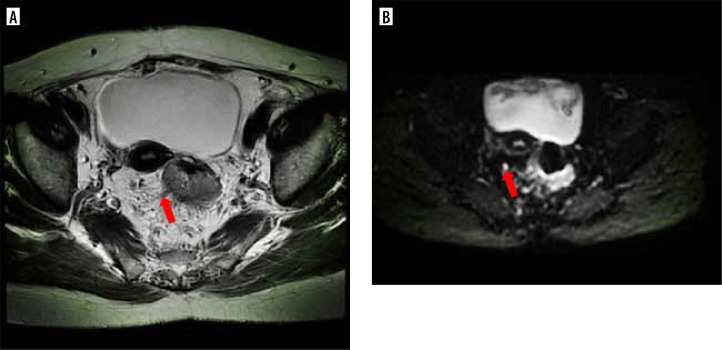

Results: 150 patients were included. Among them, 50 (33.3%) presented with vascular tumour thrombus, and 72 (48.0%) had lymph node metastasis. The detection of regional lymph nodes (DWI-LN) was an independent risk factor for lymph node metastasis. The area under curve of the nomogram model was 0.804.

Conclusion: Preoperative serum CA19.9, and the relationship between tumour and peritoneal reflection in preoperative MRI and DWI-LN have clinical value in predicting lymph node metastasis in patients with rectal cancer.